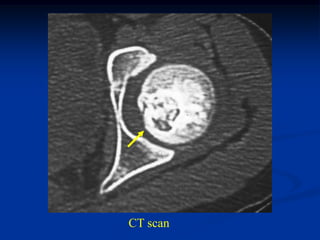

Case #594

26 year male

periosteal chondroma

proximal humerus

tumor

CT scan

small enchondroma

Coronal T-1 MRI

Photomic